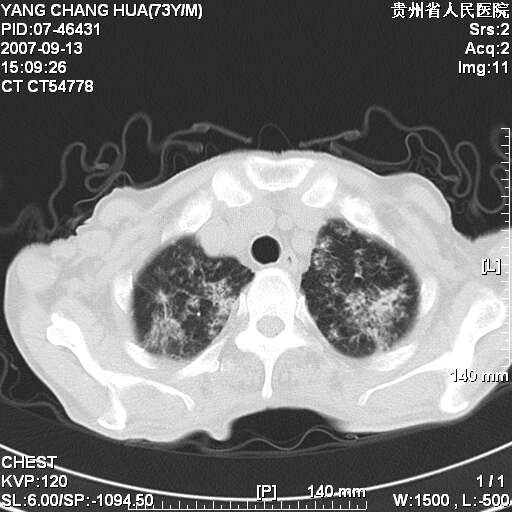

图像没有传全。肺部为感染性病灶;肺囊肿;双侧胸腔积液;肝脾肿大;腹水。

双肺部为感染性病灶.双侧胸腔积液;肝脾肿大;腹水.

双肺部为感染性病灶.双侧胸腔积液;肝脾肿大;脾脏密度不均,不除外脾侵润?腹水.

双肺点片状影,以双上肺改变明显.双侧胸腔积液.为感染性病灶,但不除外结核.

双上肺继发型肺结核。

双肺散在斑片状及多发小结节状阴影,边缘模糊,双上肺野明显,双侧胸膜腔少量积液,纵隔及肺门区未见明显肿大淋巴结,肝脾肿大,脾内见多发低密度区,结合临床考虑恶性淋巴瘤(肺内表现为肺炎肺泡型),单看影像表现,肺结核不能排除。建议结合实验室检查或表浅淋巴结活检。